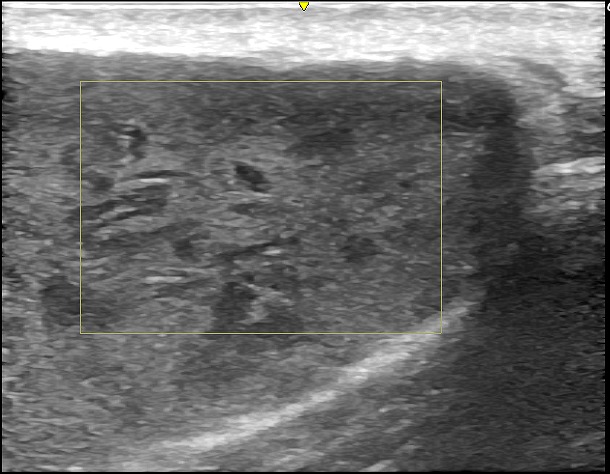

超音波ガイド下で局所麻酔薬を使用し、粉瘤の被膜を剥がした後、小さな切開で角質を排出し、被膜を完全に切除しました。巨大な粉瘤を除去したため、皮下に空間が生じましたが、浸出液がたまらないように2日間ドレーンを挿入しました。

術後半年後には、わずかな変形は認められるものの、傷跡は目立たず、超音波検査で再発がないことを確認し、治療を終了しました。